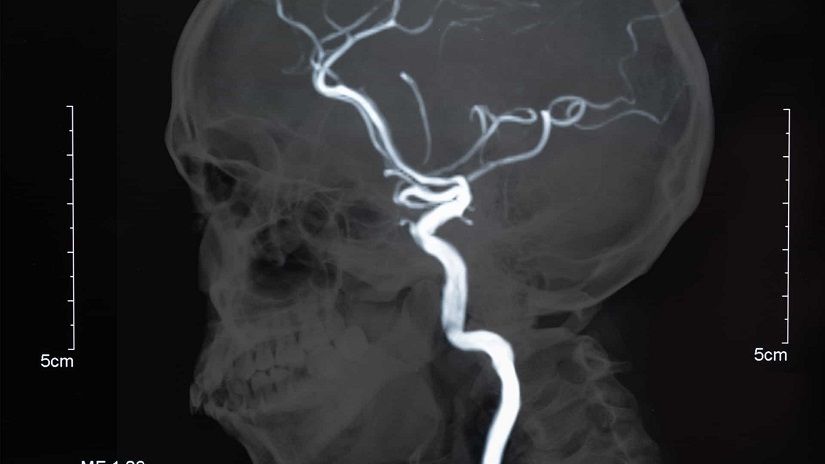

“Quando o paciente desconfia desses sintomas e procura ajuda principalmente de um Neurorradiologista Intervencionista, pode-se detectar a tempo a presença do aneurisma (que não sangrou) e tratá-lo de forma segura. A angiografia cerebral é o exame padrão-ouro, ou seja, o mais confiável para realizar o diagnóstico de um aneurisma”, explica o médico.

Portanto, todos esses pacientes deveriam realizar, a cada cinco anos, uma angiorressonância magnética cerebral (ou uma angiotomografia), um exame parecido com uma ressonância/tomografia, que mapeia o cérebro em busca de aneurismas. Esse check-up neurológico é imprescindível para o diagnóstico de aneurismas.